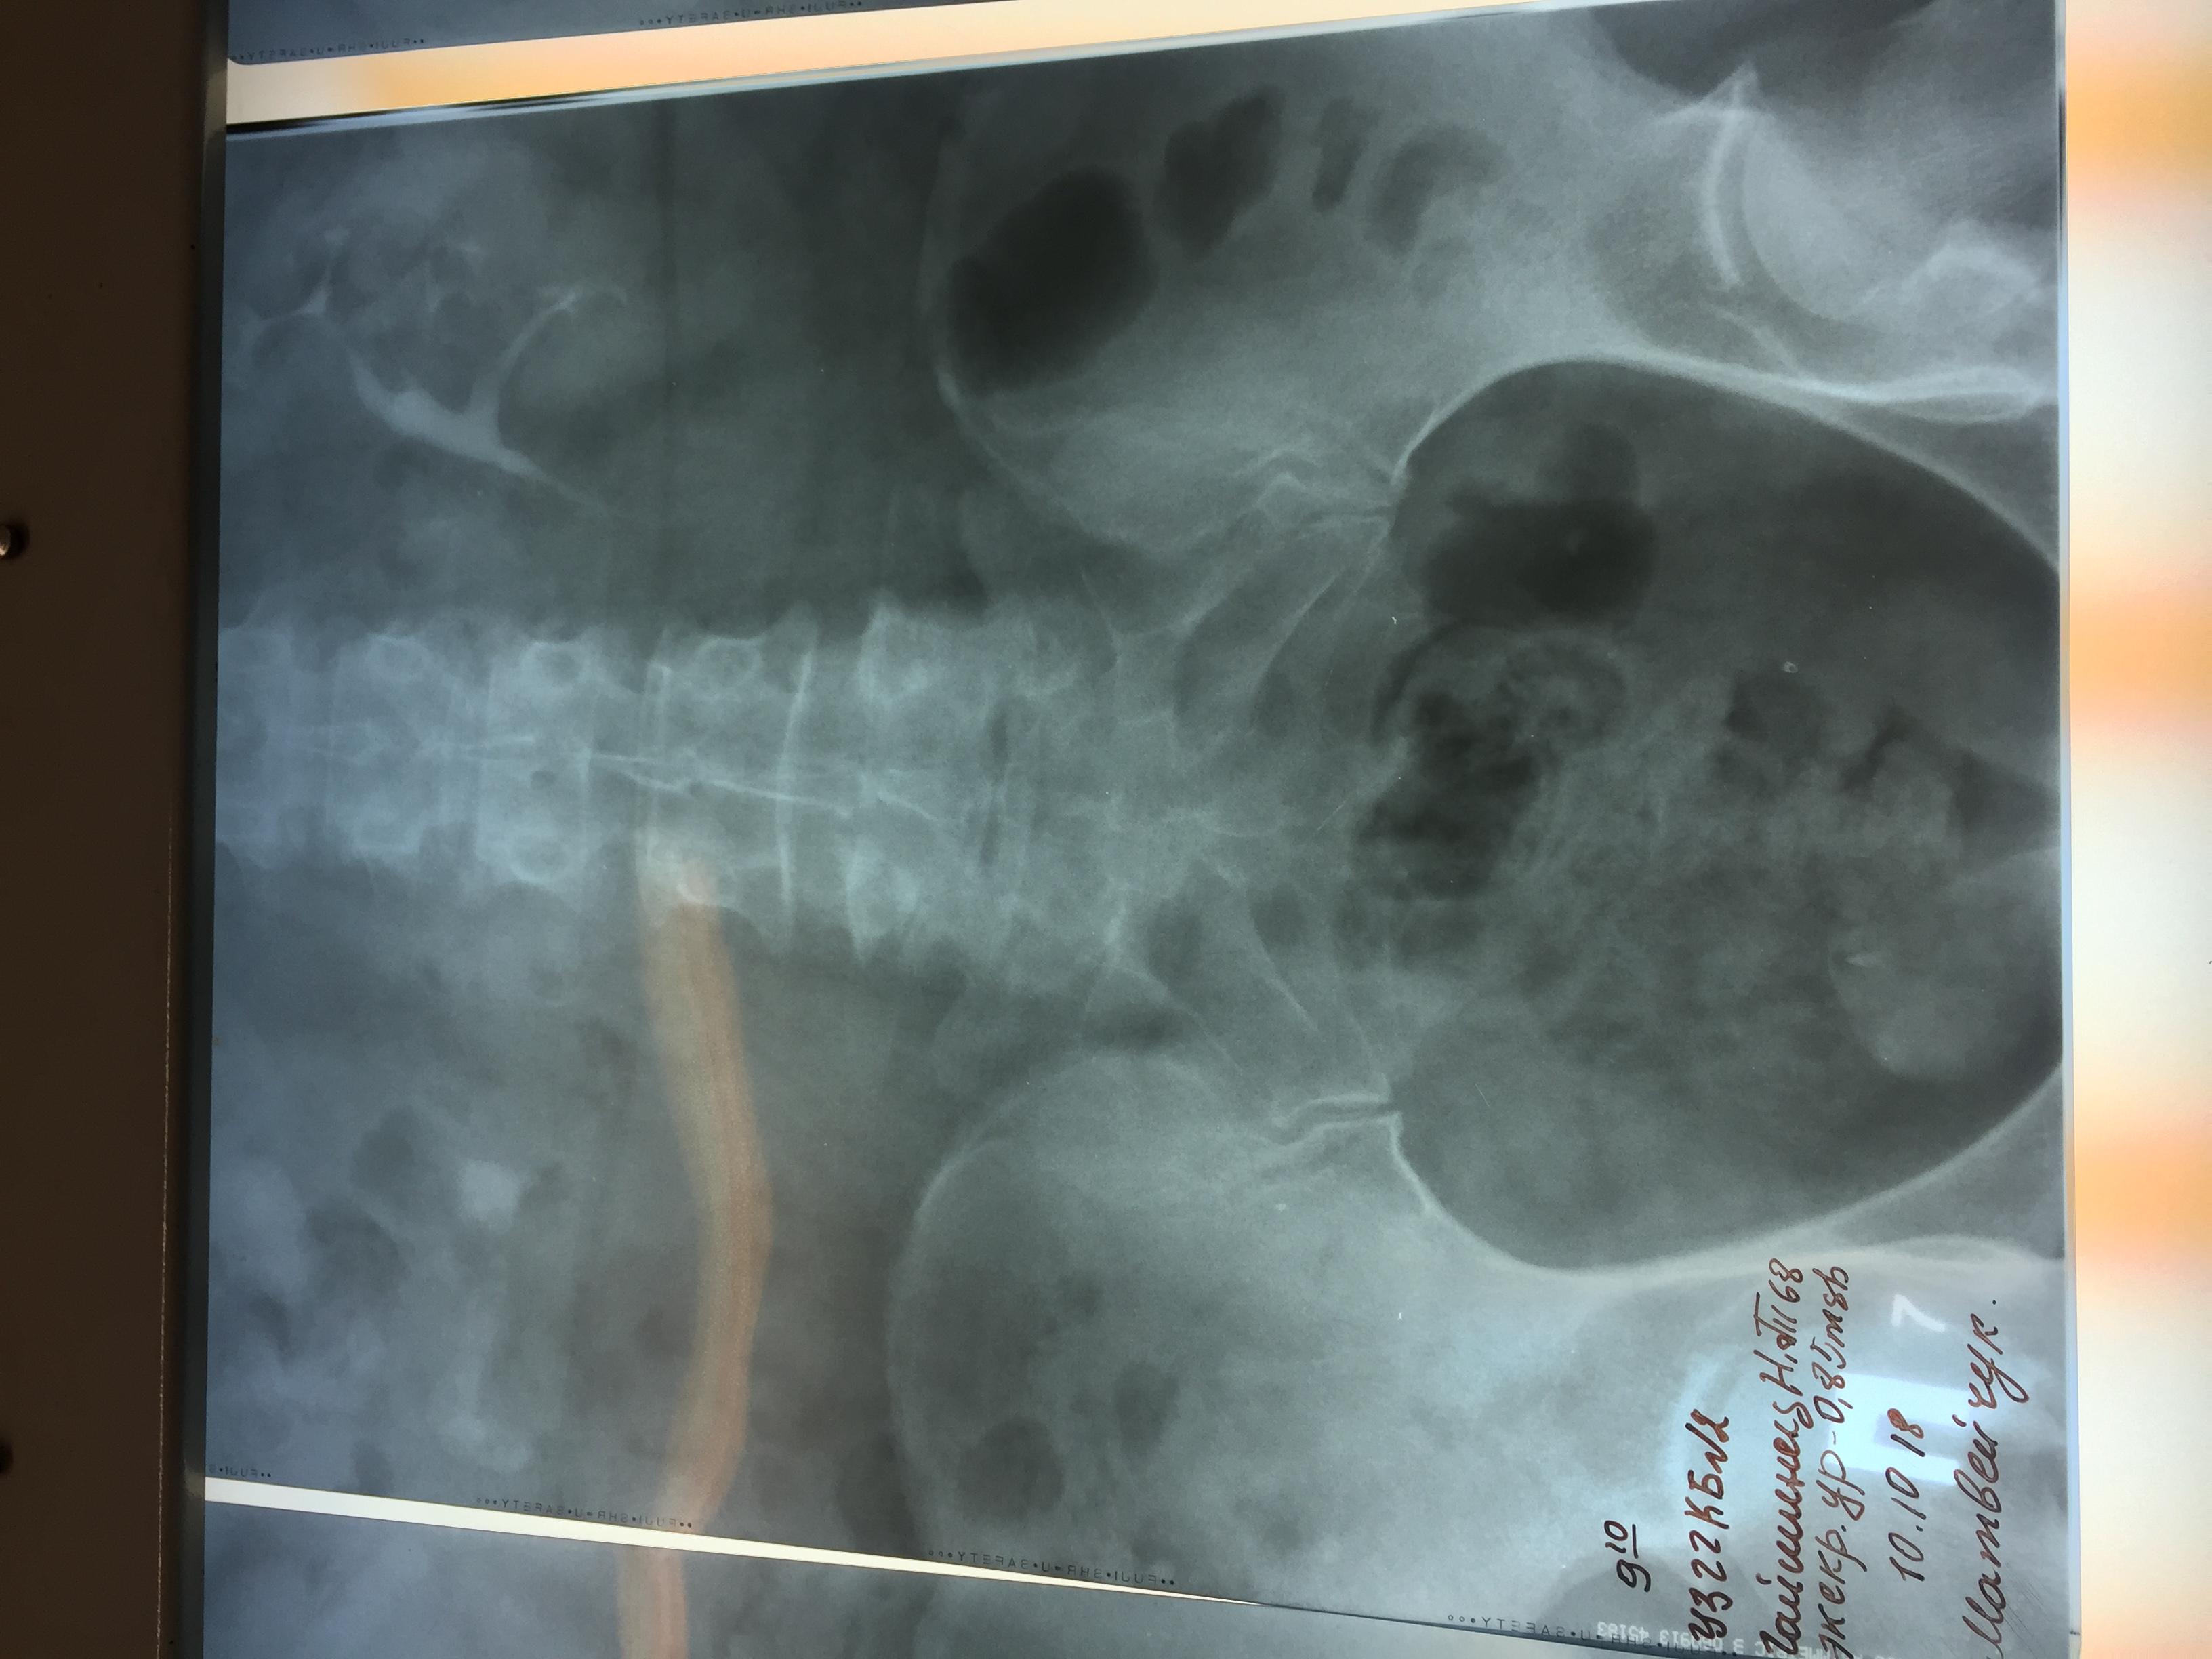

Камень в почках размер 25 мм

Беспокоила тяжесть в почке и периодические боли, часто выходили мелкие камни, после очередного приступа обратилась к врачу и попала в Больницу, сделали снимки ( фото прилагается) обнаружен крупный камень размером 25 мм и несколько мелких . Что делать? Не знаю? Дайте пожалуйста рекомендации!!! Удалять камень? Каким способом операция либо новыми технологиями это возможно?